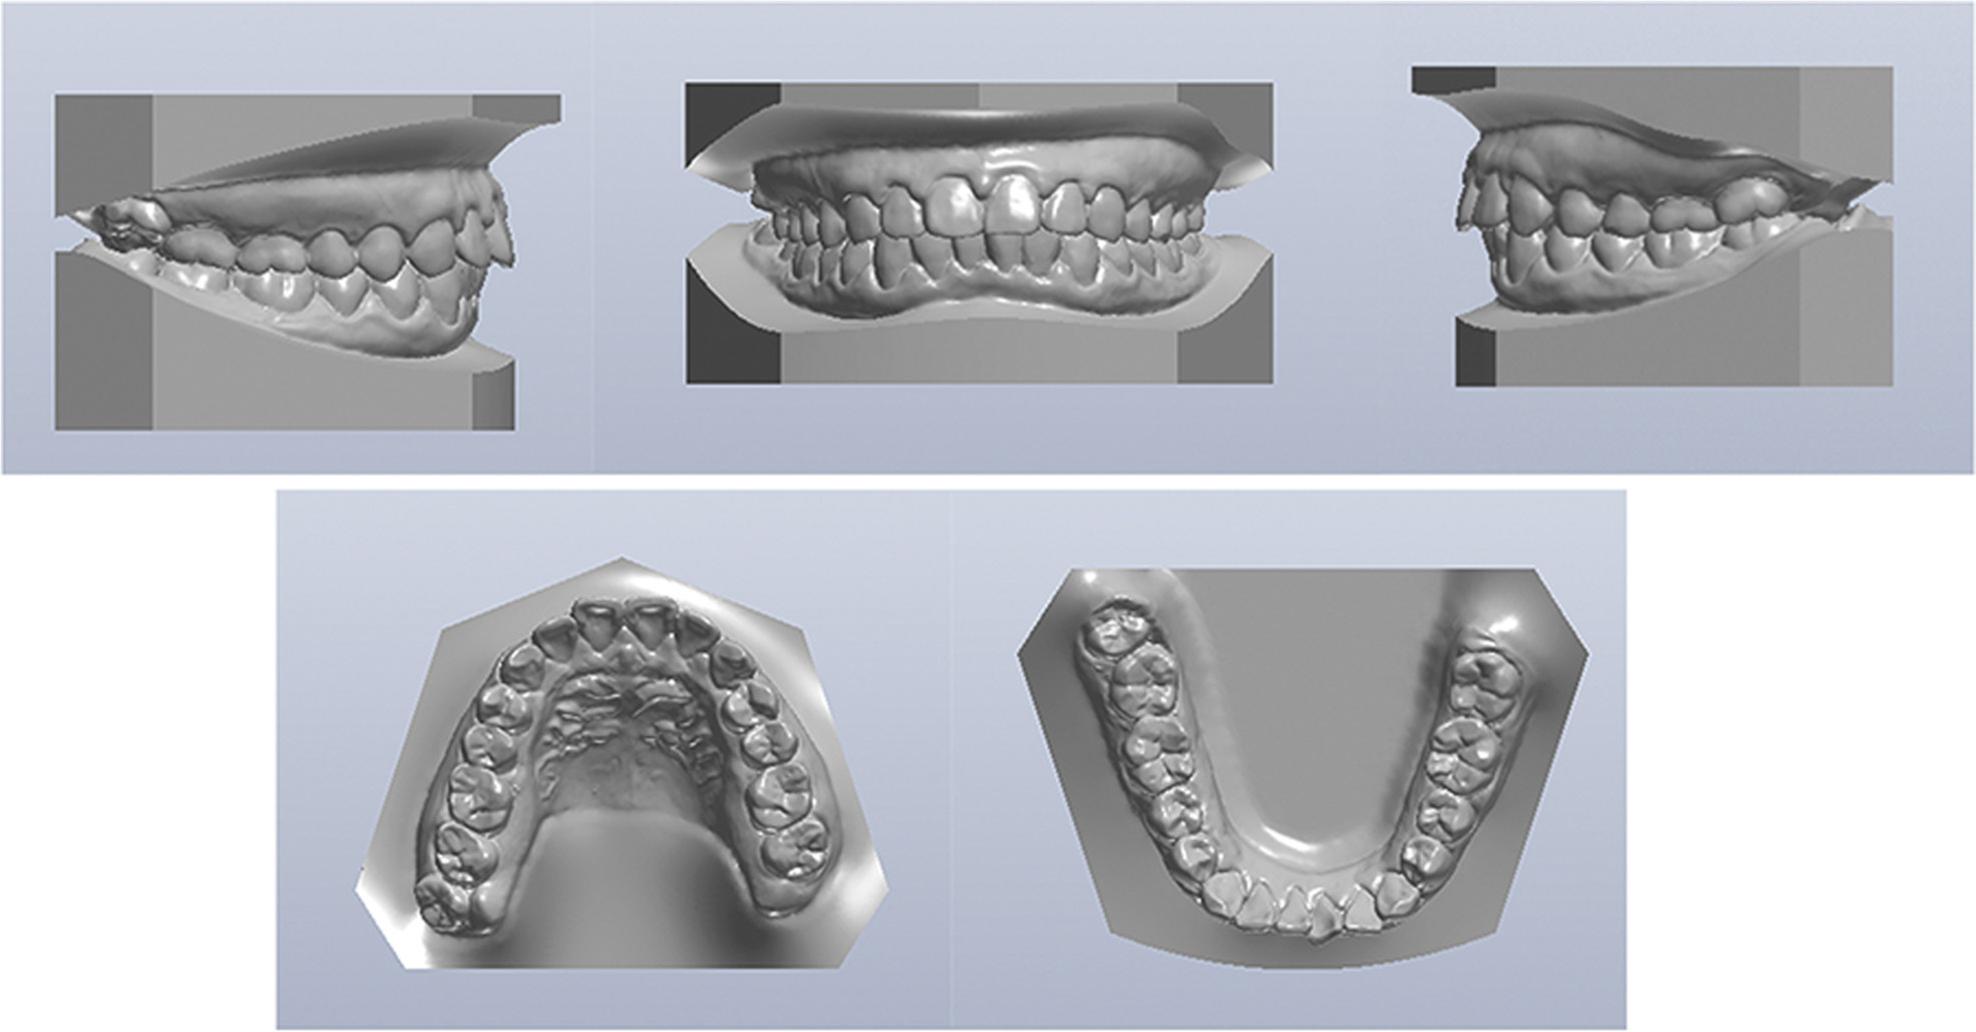

Figure 2.

Pretreatment dental models.

An intraoral examination revealed that the anterior teeth protruded and the mandibular anterior teeth were mildly crowded. The molar relationship was Class I on the right side and end-on Class II on the left side. The overjet was 6.0 mm, and overbite was 5.0 mm. The midline of the mandibular teeth deviated 1.0 mm to the left (Figure 2).